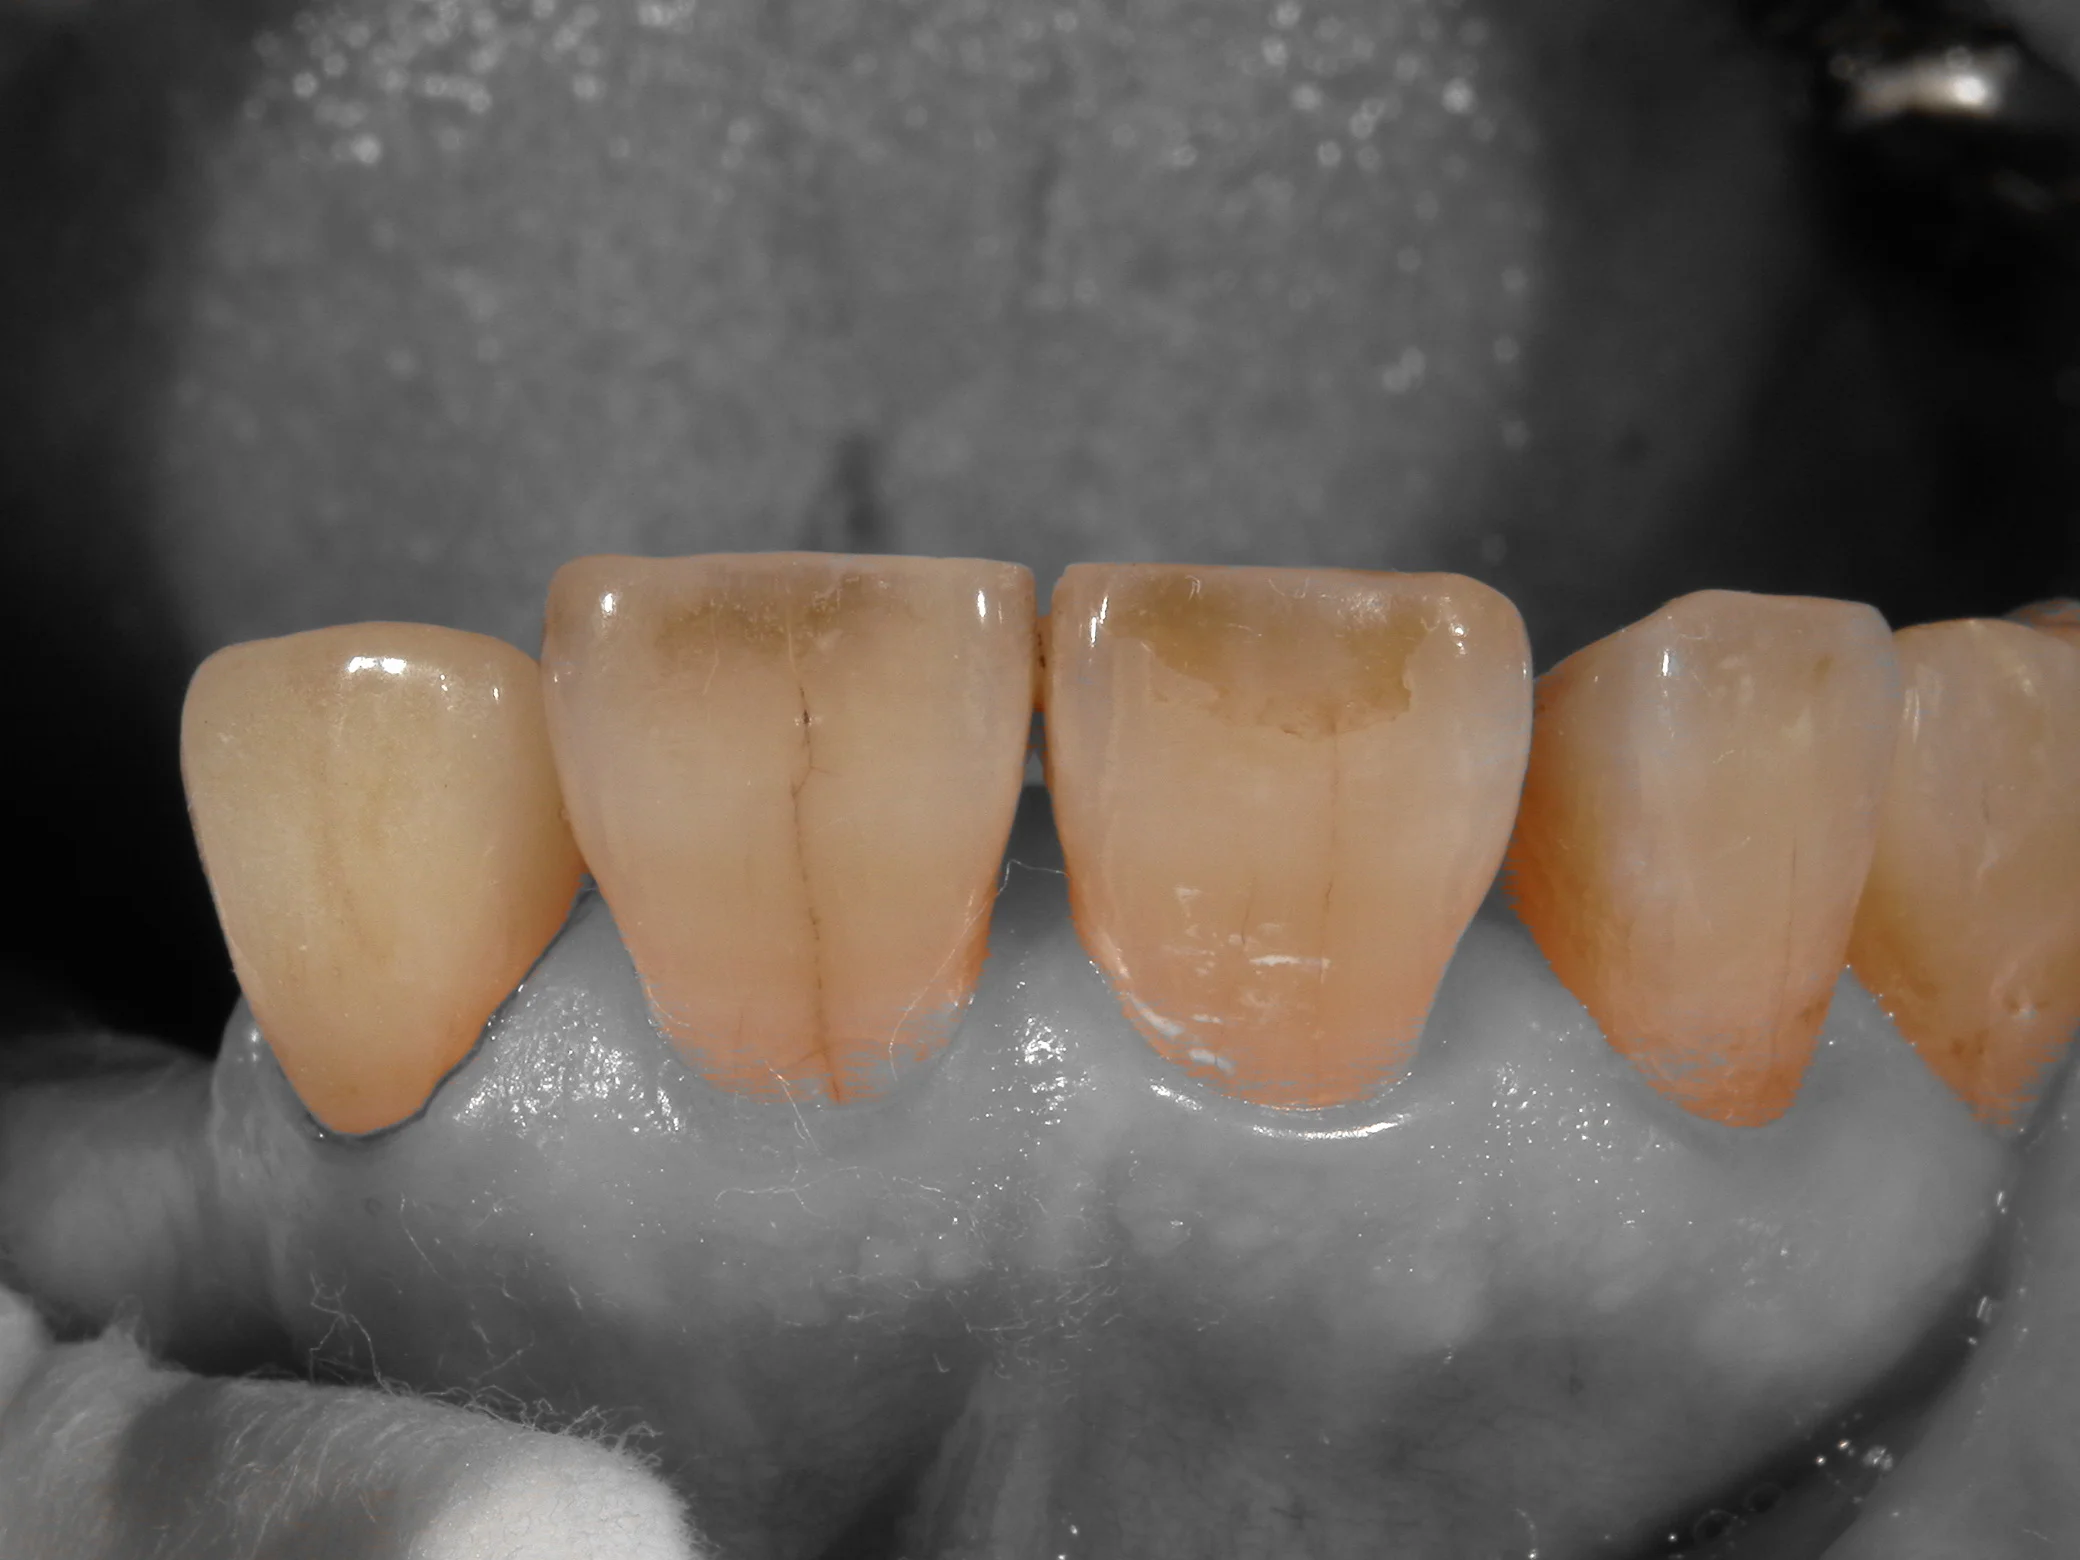

そして、上記のカメラを使用して作成したセラミックがこちらです。

セラミックでの色の再現度を上げるために・・・|坂寄歯科医院(取手市藤代) - 画像3

血液の痕で分かりやすいですが、画面の左側がセラミックです。

これをカメラの機能であるシェード抽出機能を用いて撮影するとこうなります。

セラミックでの色の再現度を上げるために・・・|坂寄歯科医院(取手市藤代) - 画像4

歯の色だけピックアップしてくれるので、前後の歯と色を合わせやすいんですね。